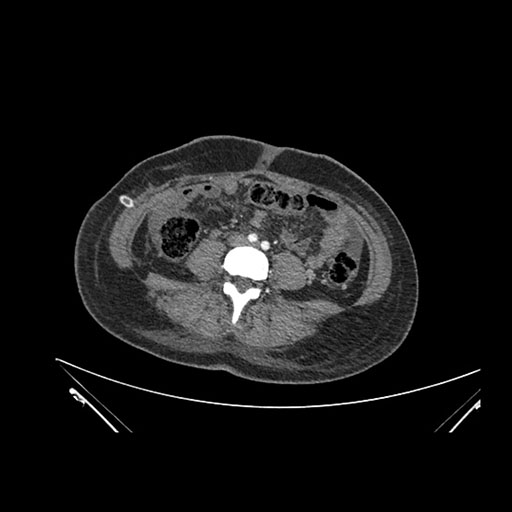

Imaging Analysis

Look through the patient's CT scan to identify any areas of concern for the necessary procedure.

Axial Venous

Based on initial findings, which issue(s) would you be most concerned about?